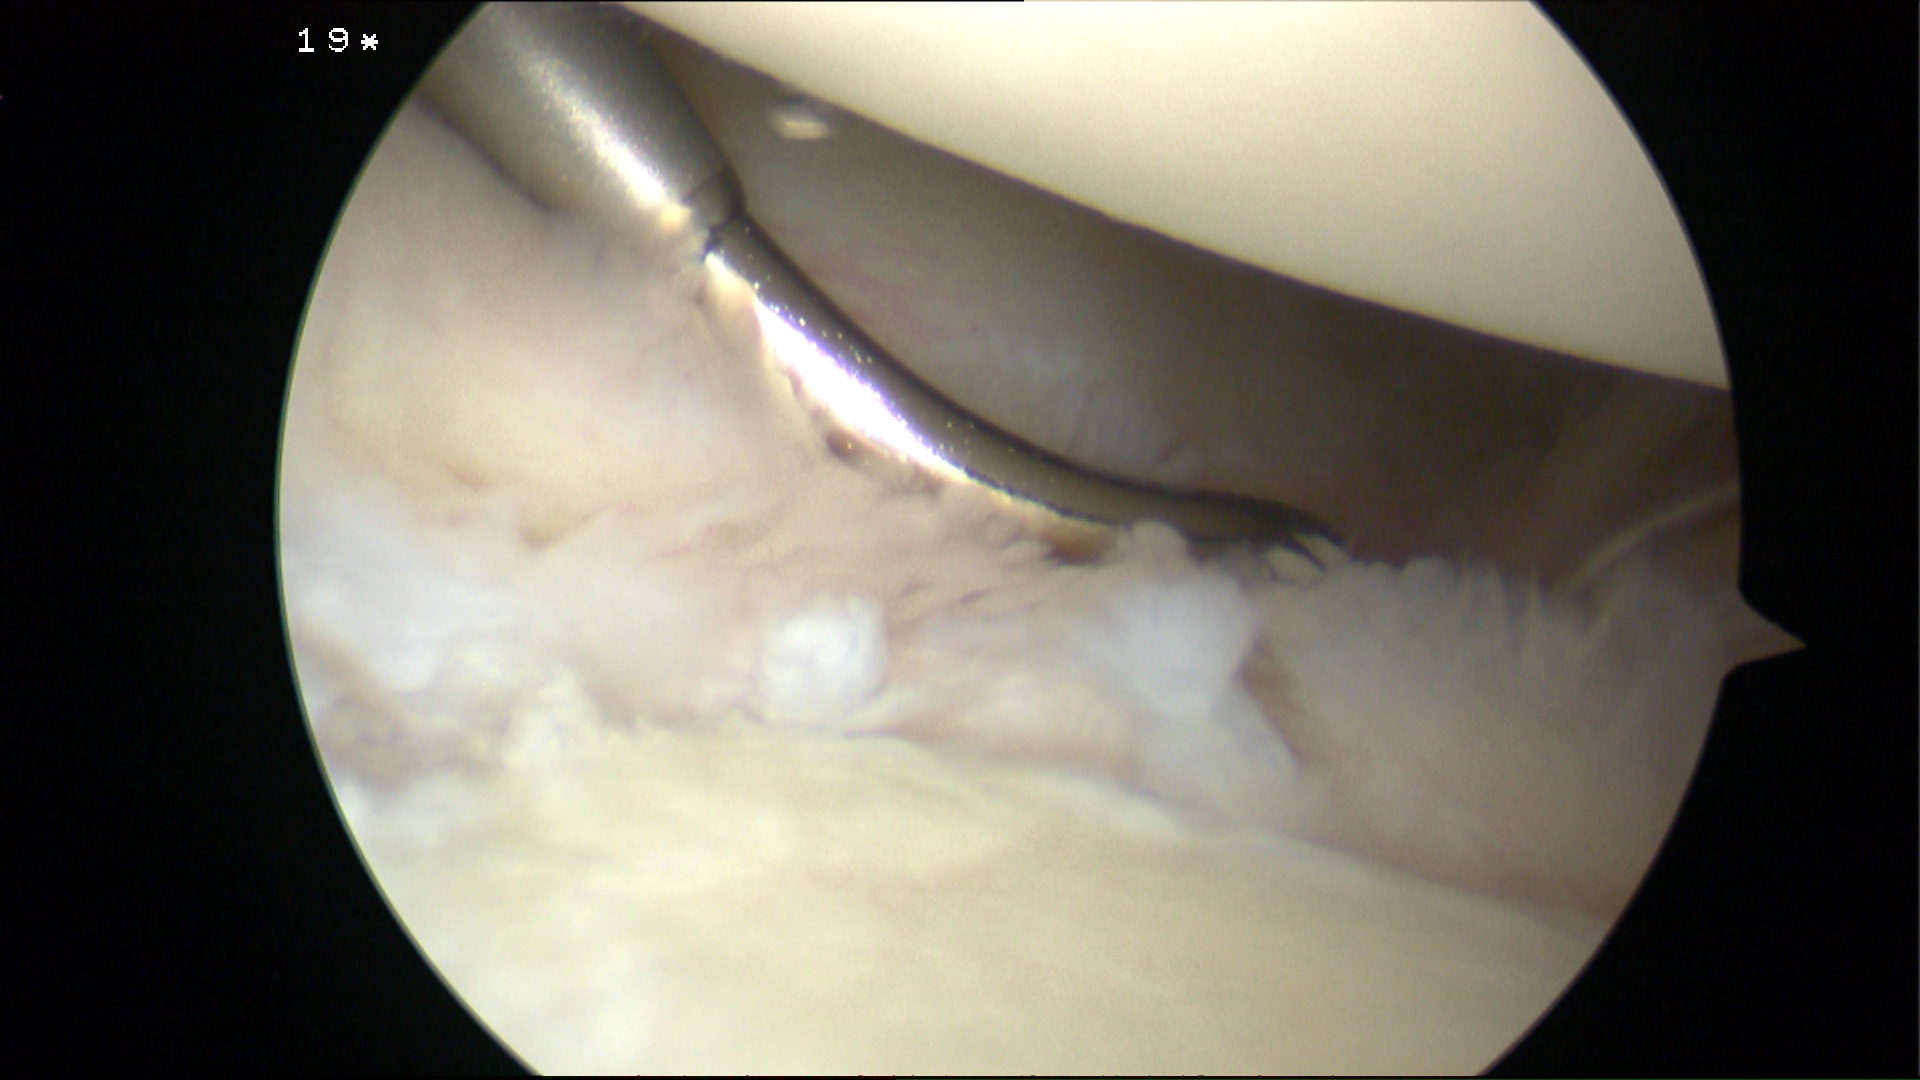

Insert anchors

Inferior anchor at 5.30 o'clock

- curved anchor guide / trans-subscapularis

- on rim of glenoid

Other anchors typically at 3 and 4 o'clock

Arthroscopy Bankart Anchor Drill GuideInferior Glenoid Anchor